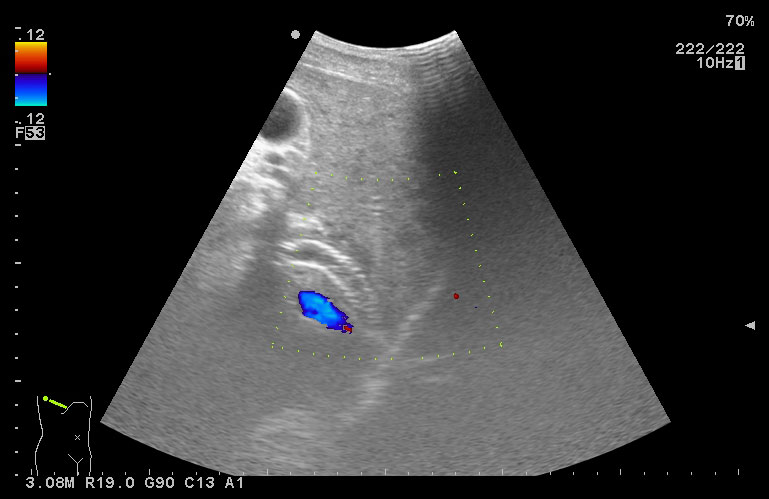

Молодой человек с циррозом печени и портальной гипертензией. Находился в стационаре в Испании, делалась какая-то манипуляция.

В печени обнаруживается какое-то инородное тело (стрелка)

TIPS, тромбоз: УЗИ

холедох стентировали?